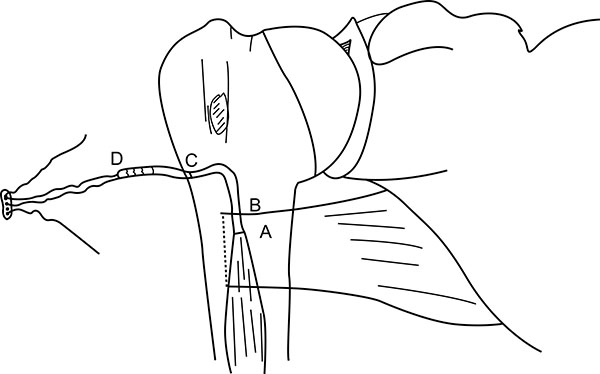

The Endo Button is loaded onto the Button deployment device and passed through bone tunnel (Figs. 4E, 3G). Once the button clears the posterior cortex, the deployment instrument can be removed while the button deploys itself, locking into place on the posterior cortex. Pulling on the sutures shuttles the LHB tendon into the humerus. The sutures are tensioned until the tendon is in contact with the posterior cortex (Fig. 3H). Finally, we advocate using a free needle to pass one suture through the tendon and tie down to the second suture to reinforce the fixation (Figs. 4F, 3I).

Unlike the use of the Biceps Button in the elbow, an additional interference screw is not required to achieve adequate fixation of the tendon. Rather, an additional suture is passed through the tendon of the LHB once it is shuttled through the humerus. This provides additional fixation strength to withstand physiologic loads. At this stage, cut the stay suture applied at superior border of pectoralis major tendon to complete the procedure. Intra-operative radiograph are taken to confirm the position of Endo Button. Wound wash is given and closed in layers. Cuff and collar is applied to support the arm for the first two weeks. Postoperative radiographs were obtained to assess the tenodesis location (Fig. 8A).